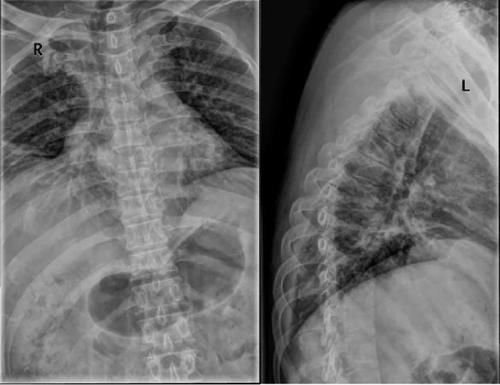

Case14:M,6y;双侧髋部疼痛1月余,加重伴不能行走半月。

文章插图